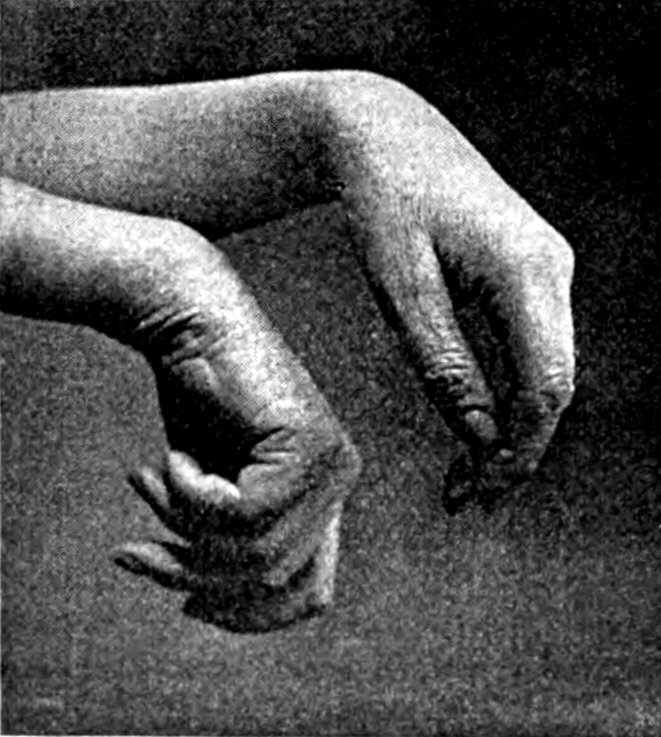

"THE HAND OF THE POTTER TREMBLES"

To lead poisoning among lead smelters, white lead workers and painters, we have grown accustomed. Now comes the revelation of wide-spread plumbism, or "potters' palsy," among workers in the potteries.

A former glost kiln-man of forty-five had worked in the Trenton potteries continuously for upwards of twenty years. Five years ago he was stricken with complete double wrist-drop and for two years was totally incapacitated.

Another practically useless pair of hands belongs to a workman forty-nine years old. Lead poisoning crippled him and deprived him of his trade at the age of thirty-three. He used to be a "ground layer." That is, he rubbed lead colors with a short brush into the surfaces to be decorated. In the course of fifteen years he had eight or ten severe attacks. In the last one, sixteen years ago, both arms were paralyzed. For two years he had to be clothed and fed. Now his arms have recovered their flexibility, but his hands still hang shrivelled and powerless to open or straighten themselves. For a livelihood he has been forced to take up an unskilled job requiring no manual work, but seven days' labor a week.

There are about 21,000 potters, the makers and enamelers of iron sanitary ware in the United States. Of these, 2,500 or over 10 per cent are declared by Dr. Alice Hamilton in her report to the United States government to be exposed in the regular course of their work to the risk of lead poisoning. Within two years 510 cases of poisoning were found.

It is now generally accepted that the one word "cleanliness" sums up the requirements for the abolition of such occurrences. Yet the workshops in the pottery and allied industries are at present almost without exception run with utter disregard of this fundamental consideration. They are as a rule dusty, ill-ventilated and poorly lighted. Washing facilities are almost unknown.